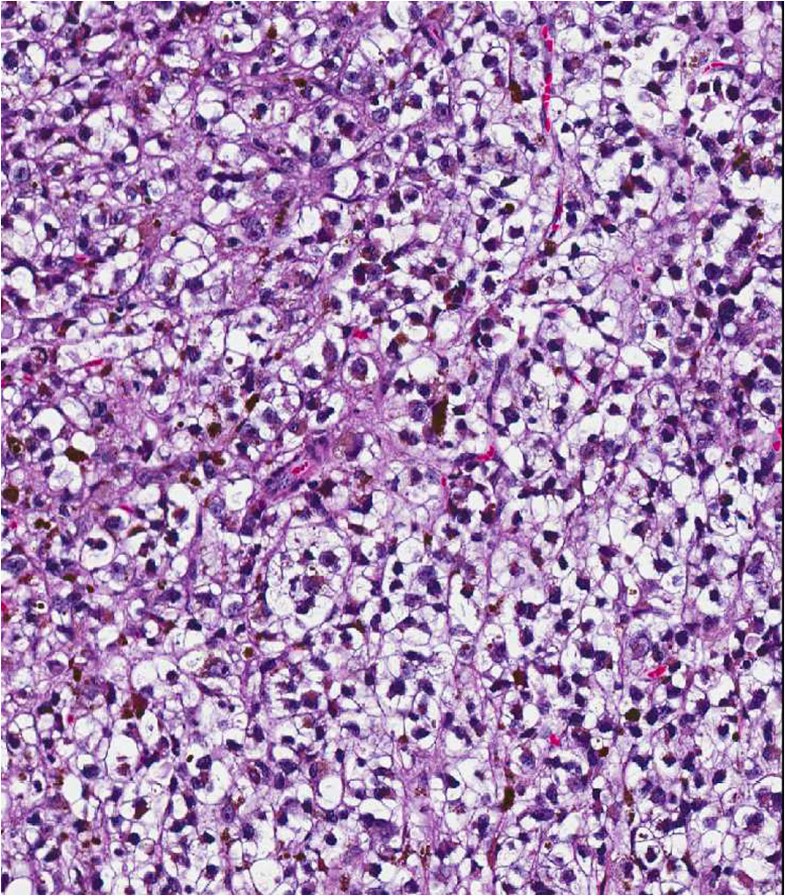

Pathology Outlines BRAF V600E Braf Mutation Uveal Melanoma In this review, we will discuss various biological aspects of melanoma related to braf mutation, including circulating and tissue. We have investigated the frequency of braf mutations at the expression level in melanomas of the uveal tract. Uveal melanoma (um) is the most common primary intraocular malignancy in adults. Instead, more than 90% of. Oncogene and tumor suppressor mutations that. Braf Mutation Uveal Melanoma.